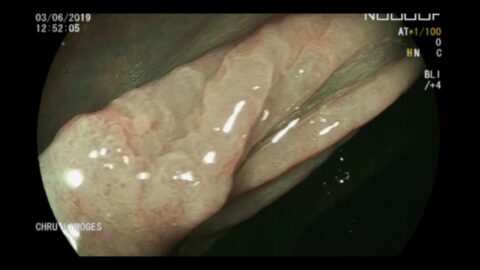

Résection par dissection sous-muqueuse d’une GIST gastrique de 3 centimètres

CFEIntervention commentée